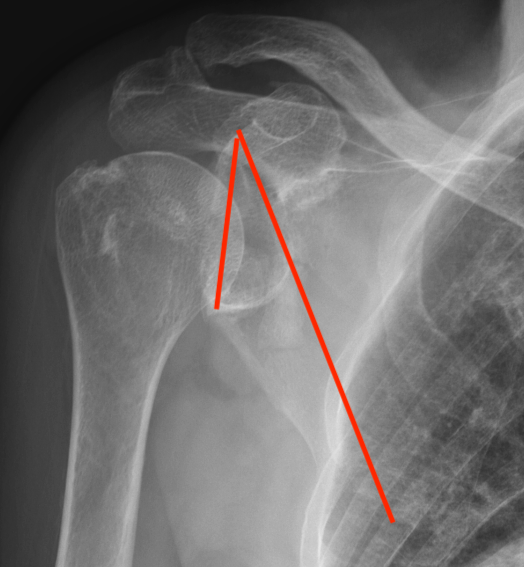

Glenopolar angle

Definition

- line connecting the superior and inferior glenoid fossa

- line connecting the superior pole of glenoid and inferior angle scapula

- normal 30 - 40 degrees